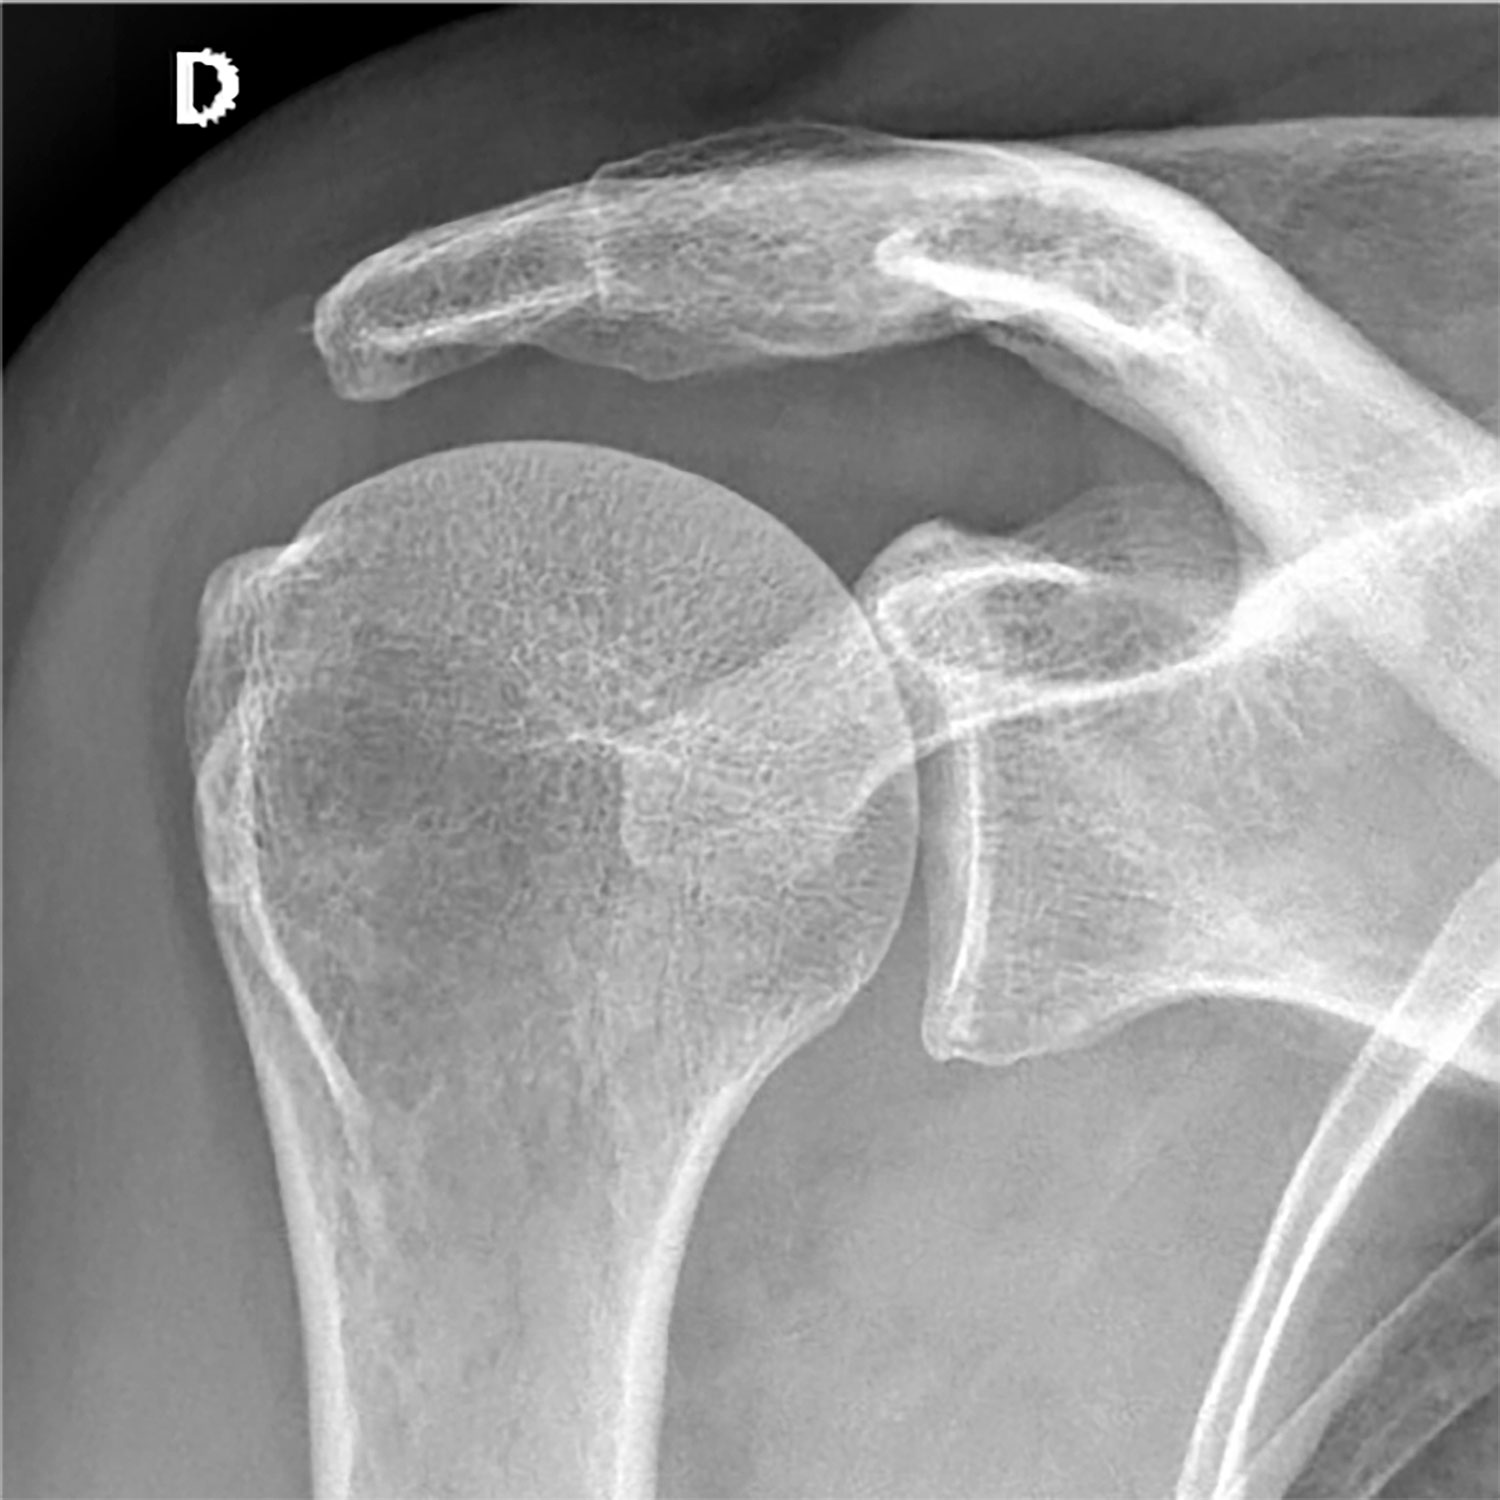

La radiographie est un examen d’imagerie médicale qui utilise les rayons X pour visualiser les structures internes de votre corps. Sa réalisation fait partie de notre cœur de métier et nécessite un savoir-faire technique et médical adapté à chaque pathologie suspectée. Différents clichés, appelés incidences,  pourront être réalisés en s’adaptant à la question posée par votre prescripteur et aux symptômes qui motivent votre venue dans notre centre.

• Certaines structures, en particulier les os ou le métal, arrêtent une partie de ces rayons.

• L’image est un négatif : les structures denses apparaissent blanches, les tissus mous apparaissent gris.

Radiographie images d'examen